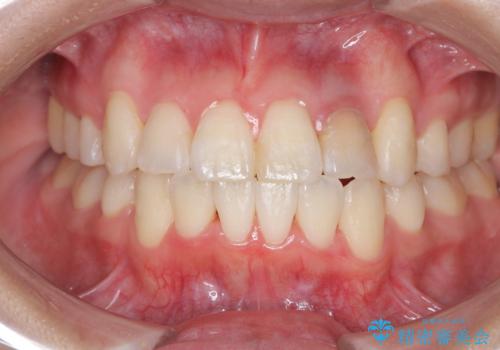

【ワイヤー矯正】八重歯 歯のでこぼこを治したい!

下顎前歯の叢生を短期間で改善

担当医 河口智英